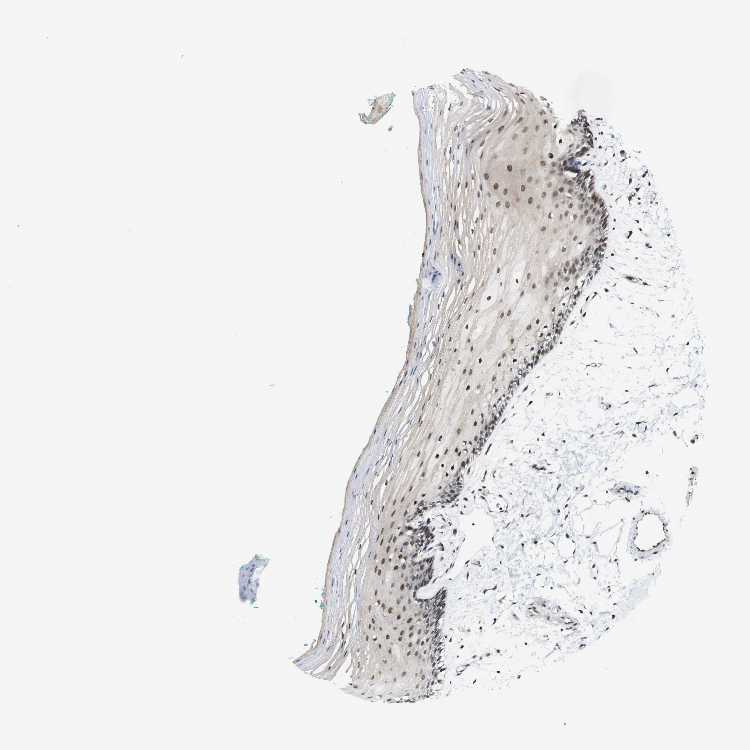

TISSUE PRIMARY DATA ORAL MUCOSA Show tissue menu

Oral mucosa

ORAL MUCOSA - Antibody stainingi

Antibody staining in the annotated cell types in the current human tissue is reported as not detected, low, medium, or high, based on conventional immunohistochemistry profiling in selected tissues. This score is based on the combination of the staining intensity and fraction of stained cells.

Each image is clickable and will lead to virtual microscopy that enables deeper exploration of all samples and also displays staining intensity scores, fraction scores and subcellular localization as well as patient and tissue information for each sample.

Antibody HPA012956Antibody HPA077702

Squamous epithelial cells MediumNot detected